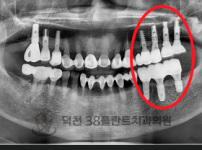

치료전후